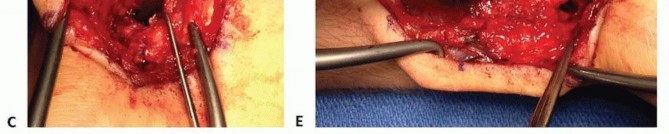

TECH FIG 4 •(continued)C. The scaphoid nonunion site (at tip of Freer elevator) is débrided to remove fibrous tissue. D. The palmar corticocancellous graft (in forceps) is rotated into the nonunion site. E. The graft is press-fit into the nonunion site and secured with internal fixation.

Periosteum on either side of the palmar carpal artery is incised, and the artery is gently mobilized laterallyto the radial artery.Bone graft harvest from the ulnar half of the distal radius is initiated by periosteal incision with a scalpel, followed by osteotomy and elevation with small osteotomes.Incision through the radioscaphocapitate ligament exposes the scaphoid nonunion site and allow for removal of fibrous tissue (TECH FIG 4C).

GRAFT PLACEMENT

The graft is rotated and fitted into the nonunion site placing the cortical bone along the palmar surface (TECH FIG 4D).The graft is press-fit between the scaphoid proximal and distal portions while avoiding the vascular pedicle. Internal fixation is used to secure the bony elements (TECH FIG 4E).Repair of the radioscaphocapitate ligament is performed prior to final soft tissue closure.Avoid compression screw fixation.1. Graft fracture often will occur.2. Kirschner wire removal facilitates imaging studies.Perform a radial styloidectomy with the dorsal approach.1. Improves exposure and reducesthe chance of graft impingementDo not exsanguinate before tourniquet inflation.1. Visibility of the irrigating artery isenhanced with blood present in the vessels.The retinaculum should be opened over the radial side of thefirst compartment and the ulnar side of the second compartment when using the 1,2 IC SRA.1. This diminishes chances ofdamaging the irrigating artery.2. Graft is harvested from the radius just distal and dorsal to the brachioradialis insertion.The palmar carpal artery lies close to the articular surface ofthe distal radius.1. Care must be taken to avoid jointviolation with graft harvest.